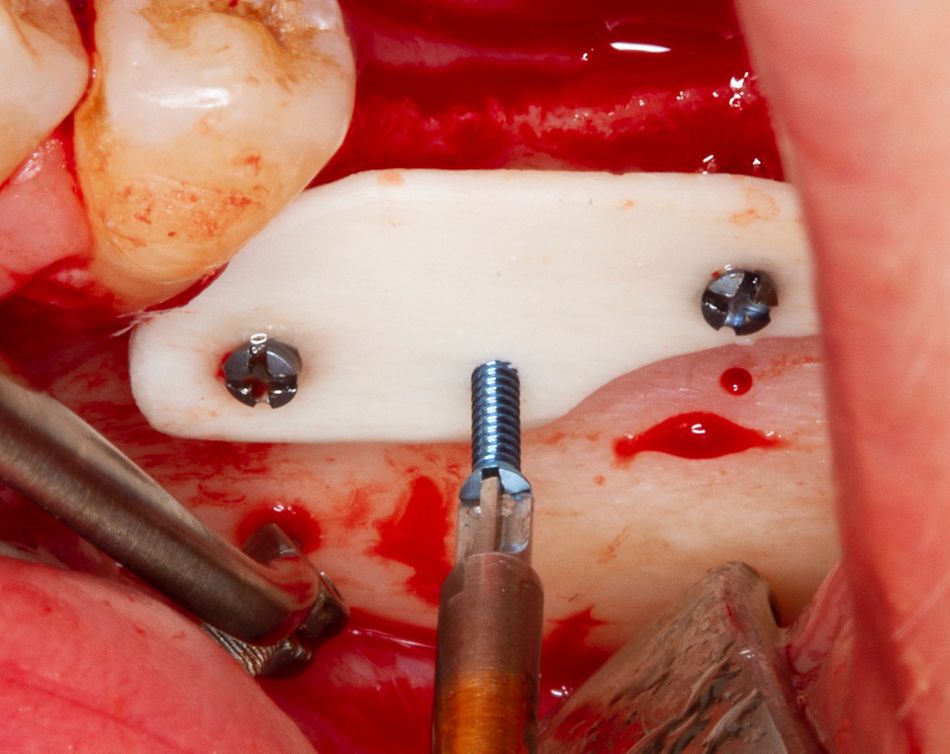

An allogeneic cortical plate (Botiss maxgraft® cortico, 25×10×1mm) was shaped and fixed with three Maxdrive screws (Figure 4).

Figure 4: Adaptation and fixation of the allogeneic shell plate